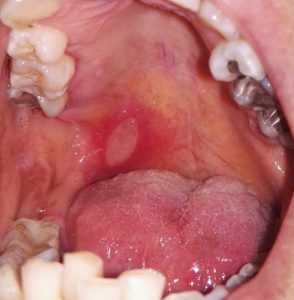

כיבים בחלל הפה כחלק ממחלות נגיפיות שכיחות

בחלל הפה, עלולים להופיע גם כיבים שמקורם זיהומי. זיהום של נגיף ההרפס סימפלקס למשל, המתבטא לרוב כפצעים שלפוחייתיים חוזרים באזור השפתיים (הרפס לביאליס, מכונה לפעמים "פצעי חום"), עלול לגרום גם לכיבים בתוך חלל הפה, בעיקר באזור החניכיים והחך. בעת ההדבקה הראשונית בנגיף זה, עלולים להופיע פצעים מפושטים בפה, בשילוב חום, חולשה והרגשה רעה, מצב השכיח בקרב פעוטות וילדים. ישנם נגיפים נוספים, העלולים לגרום למחלות השכיחות יותר בגילאי הגן, כמו הרפאנגינה או מחלת הפה והגפיים, הגורמות אף הן להופעה של פצעים בפה. מרבית המחלות האלה חולפות מעצמן תוך שבוע-שבועיים, אך חשוב מאוד להקפיד שהפעוט יאכל ובעיקר ישתה באופן הנדרש, על מנת למנוע התייבשות. כחלק מהטיפול, חשוב מאוד לשמור על היגיינת ידיים, הימנעות ממגע עם הפצעים, הפרדת כלים ומגבות ועוד, וזאת על מנת למזער את האפשרות להדבקה של בני הבית האחרים. זיהום אחר, האופייני יותר לאוכלוסייה מבוגרת ואף קשור לעיתים לירידה בתפקוד מערכת החיסון, נגרם מנגיף הוריצלה זוסטר, האחראי למחלה המוכרת בשם "שלבקת חוגרת" או "הרפס זוסטר". על אף שבמרבית המקרים, המחלה תתפרץ בגוף בצורת פצעים שלפוחייתיים המלווים בכאב עז, יתכנו מצבים בהם הנגיף פוגע באזור הראש והפנים עם הופעה של כיבים כואבים בחלל הפה. חשוב לאבחן מחלה זו בהקדם, בכדי להתאים טיפול תרופתי ואמצעים נוספים להקלה על הכאב הניכר, הנלווה לפצעים. חשוב לדעת, שמשרד הבריאות ממליץ לבני 60 ומעלה להתחסן כנגד נגיף זה, כולל גם למי שחלו בעבר בהרפס זוסטר, מאחר שניתן לחלות במחלה זו שוב.